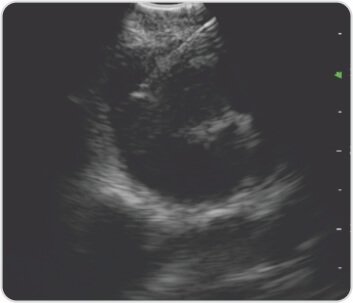

الشكل 7: العقدة المجاورة للرغامى EBUS – TBNA